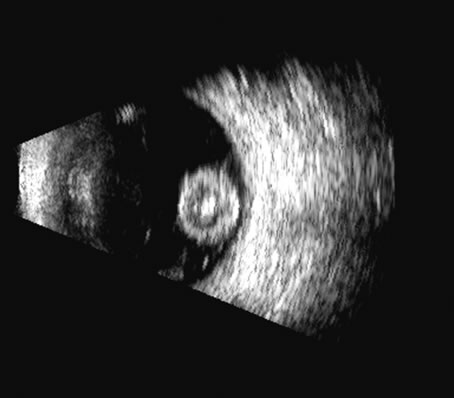

Malignant melanoma varies in its ultrasound presentation from a relatively homogeneous to heterogenous lesion on B-scan. The typical uveal melanoma absorbs sound so that the posterior section is relatively less echoic than the anterior aspect, producing a gradually decreasing amplitude, often to baseline on the A-scan (Fig. 21).

Fig. 21. An ocular tumor at the posterior pole showing the smooth convex border and solid internal reflectants typical of a melanoma.

Melanomas also have varying amounts of melanin, a highly acoustically reflective pigment. As noted, melanomas characteristically show high reflectivity anteriorly, with decreasing reflectance as the sound traverses the tissue. This produces the decreasing amplitude posteriorly in the tumor seen on A-scan and gray-scale B-scan. This effect often enhances the anterior scleral boundary. The posterior tumor border is thus measured as the first “rising” echo from the tumor decline, and it is most easily seen and accurately identified on B-scan.27